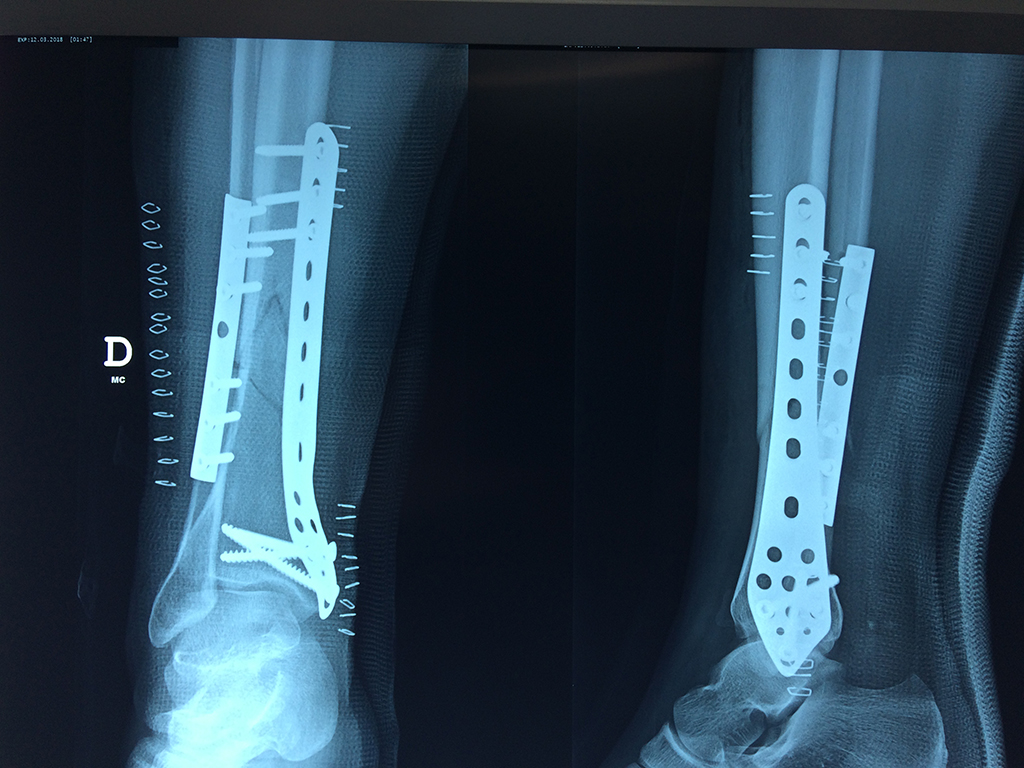

Cirugías de Tobillos

La mayor parte de las roturas implican a la parte proximal del hueso (parte del hueso próximo a la rodilla) o a la parte distal (parte del hueso cerca del tobillo).

Debido a la fina cobertura de piel que recubre la tibia y el peroné, las fracturas generalmente son abiertas, es decir, el hueso roto rasga la piel, atravesándola. Las fracturas de tibia y peroné generalmente se producen por un fuerte impacto o torsión.